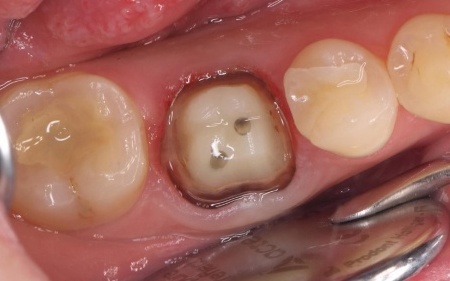

| 行ったご提案・治療内容 | 欠けた被せ物は10年以上前に治療した部位とのことで、材質はセラミックの一種であるポーセレンだと考えられます。 再び破折する危険性を考慮して、セラミックの中でも人工ダイヤモンドと呼ばれるほど高い強度をもつ「ジルコニア」での修復を提案し、同意いただきました。 メリット デメリット まずは右下奥歯の古い被せ物を除去し、歯の形を丁寧に整えます。 後日、完成した被せ物を装着し、見た目や噛み合わせに問題がないことを確認して、治療を終了しています。 |

治療中